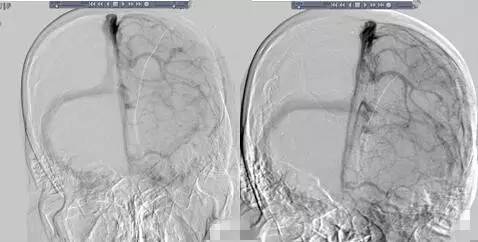

▼全颈脑血管造影术。

诊治经过:予口服华法林现PT-INR:2.45,现门诊复查随访。